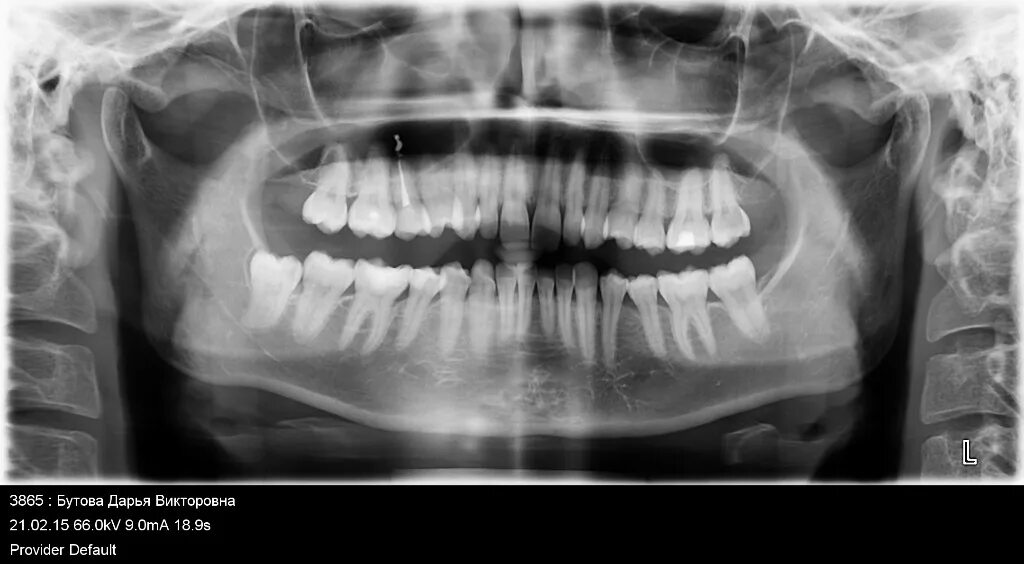

Зуб реагирует на горячее причины